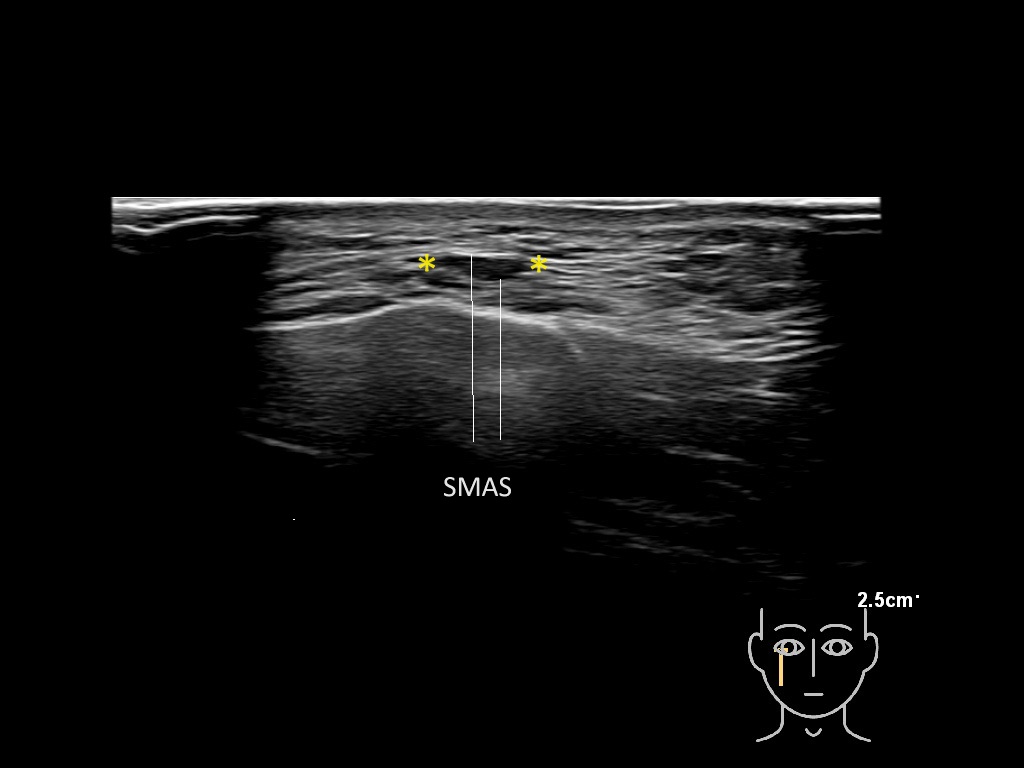

Filler deposits may end up unintentionally in the SMAS or fascial layers of the skin. Very often this will not lead to adverse events, however, adverse events ( nodules, migration / redistribution impaired muscle movement and smiling and malar edema) are are often related to filler ending up in the SMAS or fascia.

Study the first image to recognize the different layers. If you are sure about the layers, swipe to the second image to view the answer (if applicable).